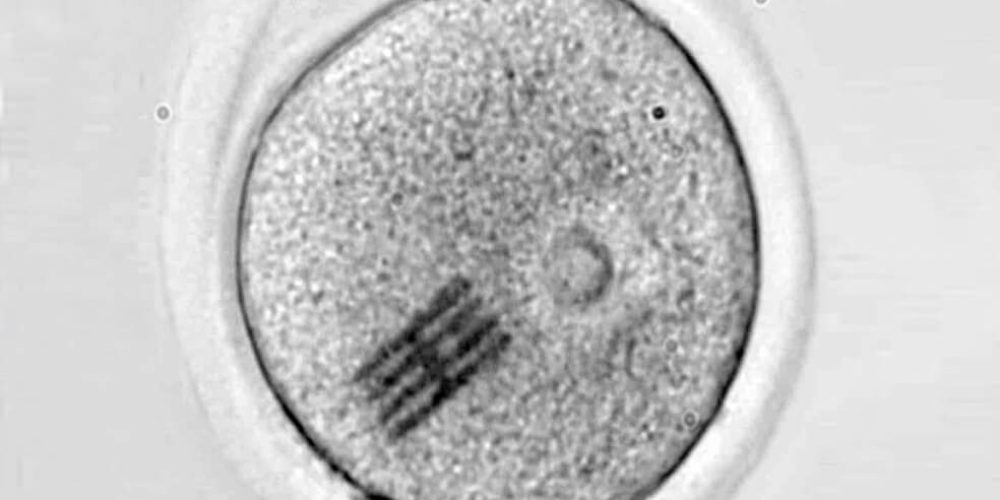

Científicos españoles y británicos han logrado inyectar diminutos sensores dentro de óvulos vivos. La manera en que se doblan estos chips permite medir las fuerzas que se generan desde que entra el espermatozoide hasta que el embrión se divide en dos células.

Investigadores del Instituto de Microelectrónica de Barcelona (IMB-CNM) del CSIC y la Universidad de Bath (Reino Unido) han fabricado e introducido chips dentro de células vivas para detectar los cambios mecánicos que se producen en las primeras etapas del desarrollo embrionario. Los detalles los publican esta semana en la revista Nature Materials.

El chip funciona como sensor mecánico y es extremadamente minúsculo: mide apenas 22 por 10,5 micrometros, con 25 nanometros de grosor. Esto significa que tiene una longitud tres veces más pequeña que el diámetro de un cabello humano, y un espesor tres veces menor que el de un virus como el SARS-CoV-2.

Los dispositivos se han fabricado en la sala blanca del IMB-CNM bajo la supervisión del científico José Antonio Plaza. Luego, en un laboratorio de la Universidad de Bath, otro equipo dirigido por Anthony C. F. Perry ha inyectado el chip junto con un espermatozoide en el interior de un óvulo de ratón para analizar las etapas tempranas de la fertilización. Este proceso inicial ocurre de forma similar en los humanos.

Con el dispositivo dentro, han podido medir las fuerzas que reorganizan el interior del óvulo, es decir, su citoplasma, desde que se introduce el espermatozoide hasta que se divide en dos células.

“Haciendo un símil con el baile, el embrión realiza una coreografía de movimientos durante su desarrollo y hemos visto que no sólo el movimiento es importante sino también la intensidad del mismo”, comenta Plaza, “y a través de microscopia, podemos ver cómo el chip se dobla en el interior de la célula”.

“Dado que hemos modelizado y conocemos perfectamente qué fuerza hay que aplicar para que se doble el chip de una determinada manera –añade–, visualizando la curvatura podemos inferir qué fuerzas mecánicas se están dando en el interior celular”.